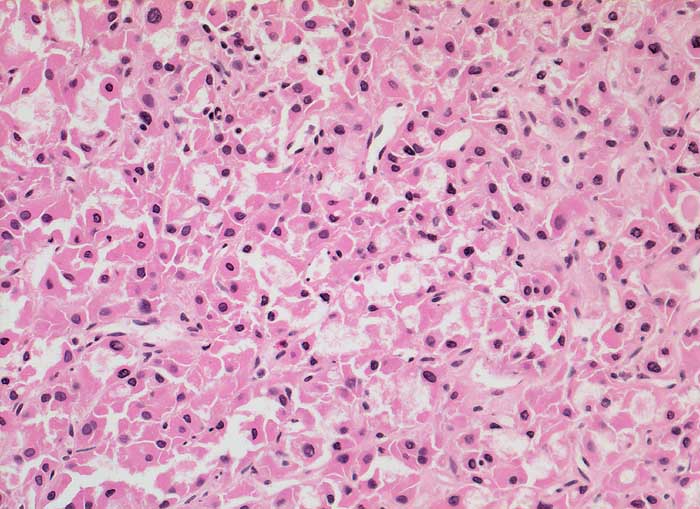

PathoPic – image database / PathoPic ID 5848 - onkozytäres Schilddrüsenkarzinom

onkozytäres Schilddrüsenkarzinom

maligner Tumor

Schilddrüse

Endokrinium

Mikrofollikulärer Tumor aus leicht polymorphen onkozytären Zellen.

Verdacht auf Schilddrüsenkarzinom

Histologie

200